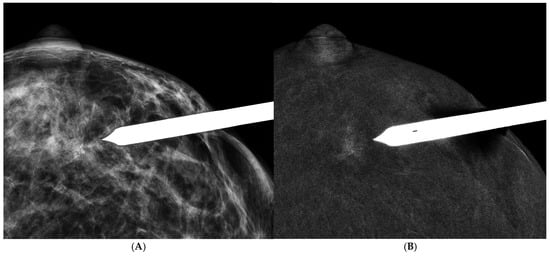

3.6. CEM-Guided Biopsy

- Tang, Y.C.; Cheung, Y.C. Contrast-enhanced mammography-guided biopsy: Technique and initial outcomes. Quant. Imaging Med. Surg. 2023, 13, 5349–5354. [Google Scholar] [CrossRef]

- James, J. Contrast-enhanced spectral mammography (CESM)-guided breast biopsy as an alternative to MRI-guided biopsy. Br. J. Radiol. 2022, 95, 20211287. [Google Scholar] [CrossRef] [PubMed]

- Cheung, Y.C.; Kuo, W.L.; Lee, L.Y.; Tang, Y.C. A case report of breast cancer in silicone-injected breasts diagnosed by an emerging technique of contrast-enhanced mammography-guided biopsy. Front. Oncol. 2022, 12, 884576. [Google Scholar] [CrossRef] [PubMed]